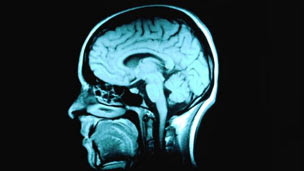

Getty Images

O cérebro humano é um dos organismos mais complexos do universo e apesar dos esforços dos cientistas, a massa cinzenta que habita nossas cabeças ainda guarda muitos mistérios.

Nos parágrafos a seguir, especialistas ouvidos pela BBC tentam, porém, romper com alguns mitos e inverdades a respeito do cérebro humano e do seu funcionamento.